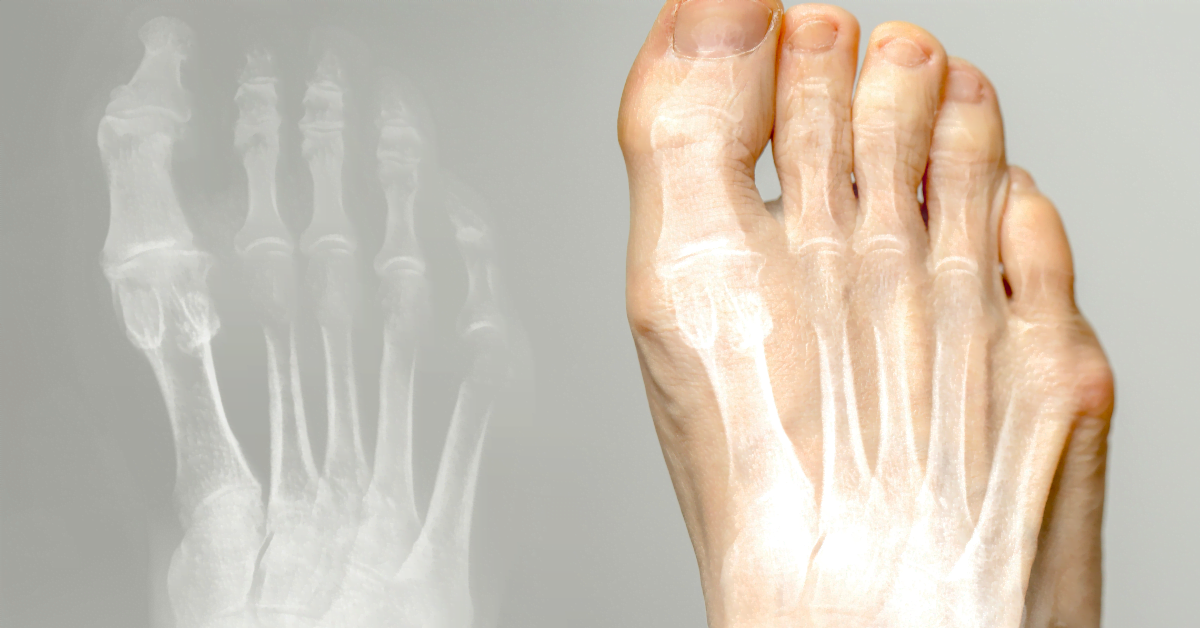

Hallux valgus (knobbelteen) is een aandoening waarbij de grote teen naar binnen wijst en een knobbeltje vormt aan de basis. Het kan pijn en ongemak veroorzaken. Hier lees je oorzaken, behandeling en preventie.

De grote teen buigt naar de andere tenen, waardoor een voetknobbel ontstaat. Oorzaken: smalle schoenen, hoge hakken, erfelijkheid, platvoeten of artritis. Slecht schoeisel veroorzaakt druk en wrijving, wat kan leiden tot slijmbeursontsteking.

Knobbel aan de basis van de grote teen, pijn bij het dragen van schoenen, roodheid en zwelling. Brandend gevoel, moeite met lopen. Soms artrose in de grote teen.

Hallux valgus is een scheefstand van de grote teen naar binnen, met een knobbel aan de basis. Vaak door smalle schoenen, hoge hakken of erfelijkheid. Kan pijn en slijmbeursontsteking veroorzaken.